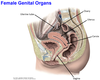

1? 2?

1? 2? 3?

1? 2?

1? 2?

3? 4?

4? 5? 6?

4? 5?

3? 4?

1? 2?